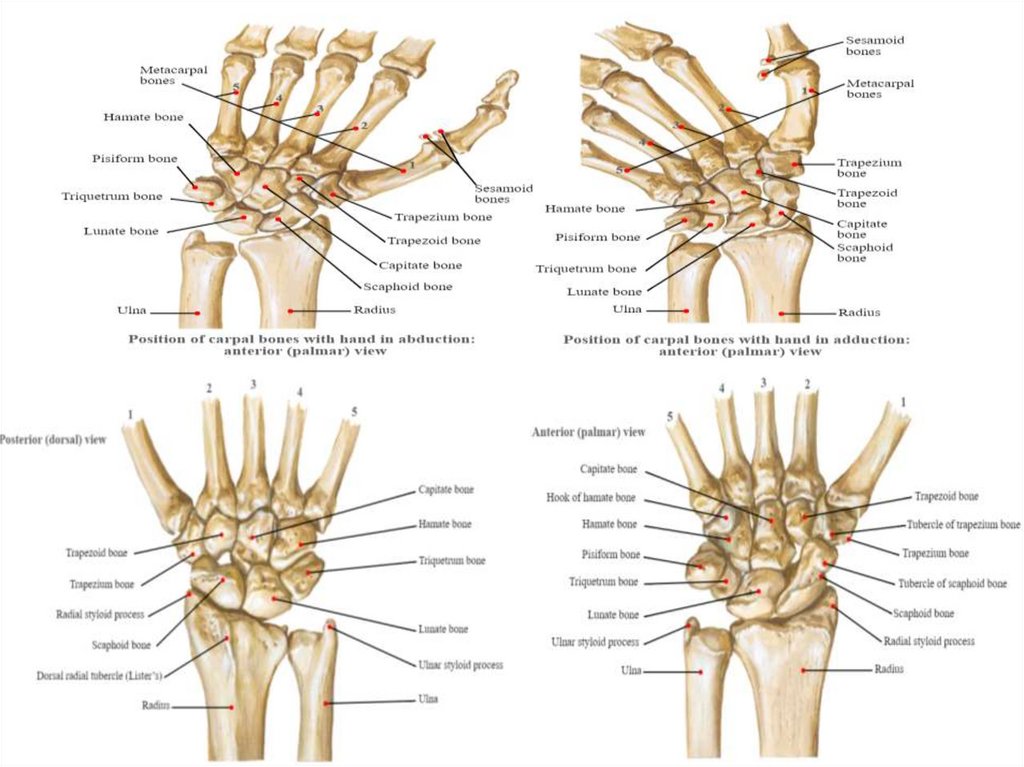

Кістки кисті – ossa manus, поділяються на зап’ясткові кістки,

п’ясткові кістки і кістки пальців, фаланги.

Зап’ясткові кістки

розміщуються в два ряди по

4 кістки в кожному і

утворюють проксимальний

і дистальний ряди.

У верхньому

(проксимальному) ряді з

латеральної в медіальну

сторону розташовані:

1) Човноподібна кістка – має

горбок човноподібної кістки;

2) Півмісяцева кістка;

3) Тригранна кістка;

4) Горохоподібна кістка.

Нижній, дистальний ряд складається з кісток які розташовані з

латеральної в медіальну сторону:

- кістка-трапеція (має горбок

кістки-трапеції);

- трапецієподібна кістка;

- головчаста кістка;

- гачкувата кістка (має гачок

гачкуватої кістки).

42.

Кістка-трапеція перша в дистальному ряді кісток зап’ястка і

з’єднується з першою п’ястною кісткою. Трапецієподібна (2)

розміщується між трапецією та головчастою кісткою. Головчаста (3)

розміщується в середині нижнього ряду і являється найбільшою із

кісток зап’ястка. Гачкувата (4) кістка виділяється зі сторони

долонної поверхні своїм гачкоподібним відростком.

утворюють

борозну зап’ястка.

Кістки зап’ястка – ossa carpi

1. Човноподібна кістка – os scaphoideum

2. Півмісяцева кістка – os lunatum

3. Тригранна кістка – os triquetrum

4. Горохоподібна кістка – os pisiforme

5. Кістка-трапеція – os trapezium

6. Трапецієподібна кістка – os trapezoideum

7. Головчаста кістка – os capitatum

8. Гачкувата кістка – os hamatum